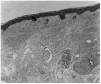

En el estudio histopatológico de la lesión se evidenció una epidermis dentro de la normalidad con esclerosis dérmica y del tejido celular subcutáneo, constituida por anchas bandas horizontales de colágeno. Llamaba la atención la ausencia de glándulas sebáceas (fig. 2).

Fig. 2.--Epidermis dentro de la normalidad. Esclerosis de la dermis y del tejido celular subcutáneo sustituido por bandas de colágeno horizontales. Destaca la ausencia de glándulas sebáceas.